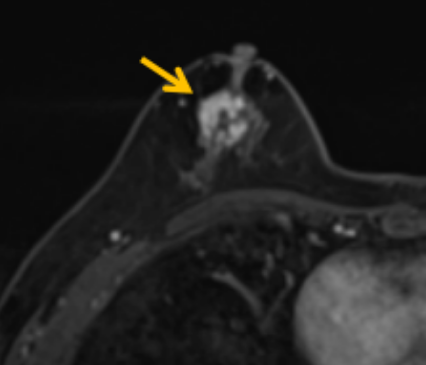

陳寶瑩評估圖像后發(fā)現(xiàn)病變?yōu)閮H僅在磁共振增強時顯示,為非腫塊樣病變,比較散,必須取得足夠多的組織才能確保病理檢查的準確性,常用的核芯針活檢獲取的組織較少,因此最終確定了磁共振引導下行真空輔助抽吸旋切活檢。取得患者及家屬認可后,陳寶瑩帶領團隊開始進行術前準備。

針對患者乳房小固定難度大這一問題,陳寶瑩通過巧妙體位和固定器的調整,順利固定好乳房。經(jīng)過磁共振多模態(tài)掃描,陳寶瑩找出病變活性成分相對集中區(qū)域,精準確定穿刺路徑,置入引導針、旋切針,到位后多角度旋切取出足量組織,拔除旋切針后即時行磁共振掃描,精準取得組織且術區(qū)出血很少,遂加壓包扎,整個過程非常順利,旋切活檢后患者回家休息。兩天后隨訪,李女士沒有任何不適,五天后皮膚上幾毫米的小切口已經(jīng)愈合。最終病理結果證實為乳腺導管原位癌,為早期乳腺癌,為患者后續(xù)針對性治療奠定了基礎。